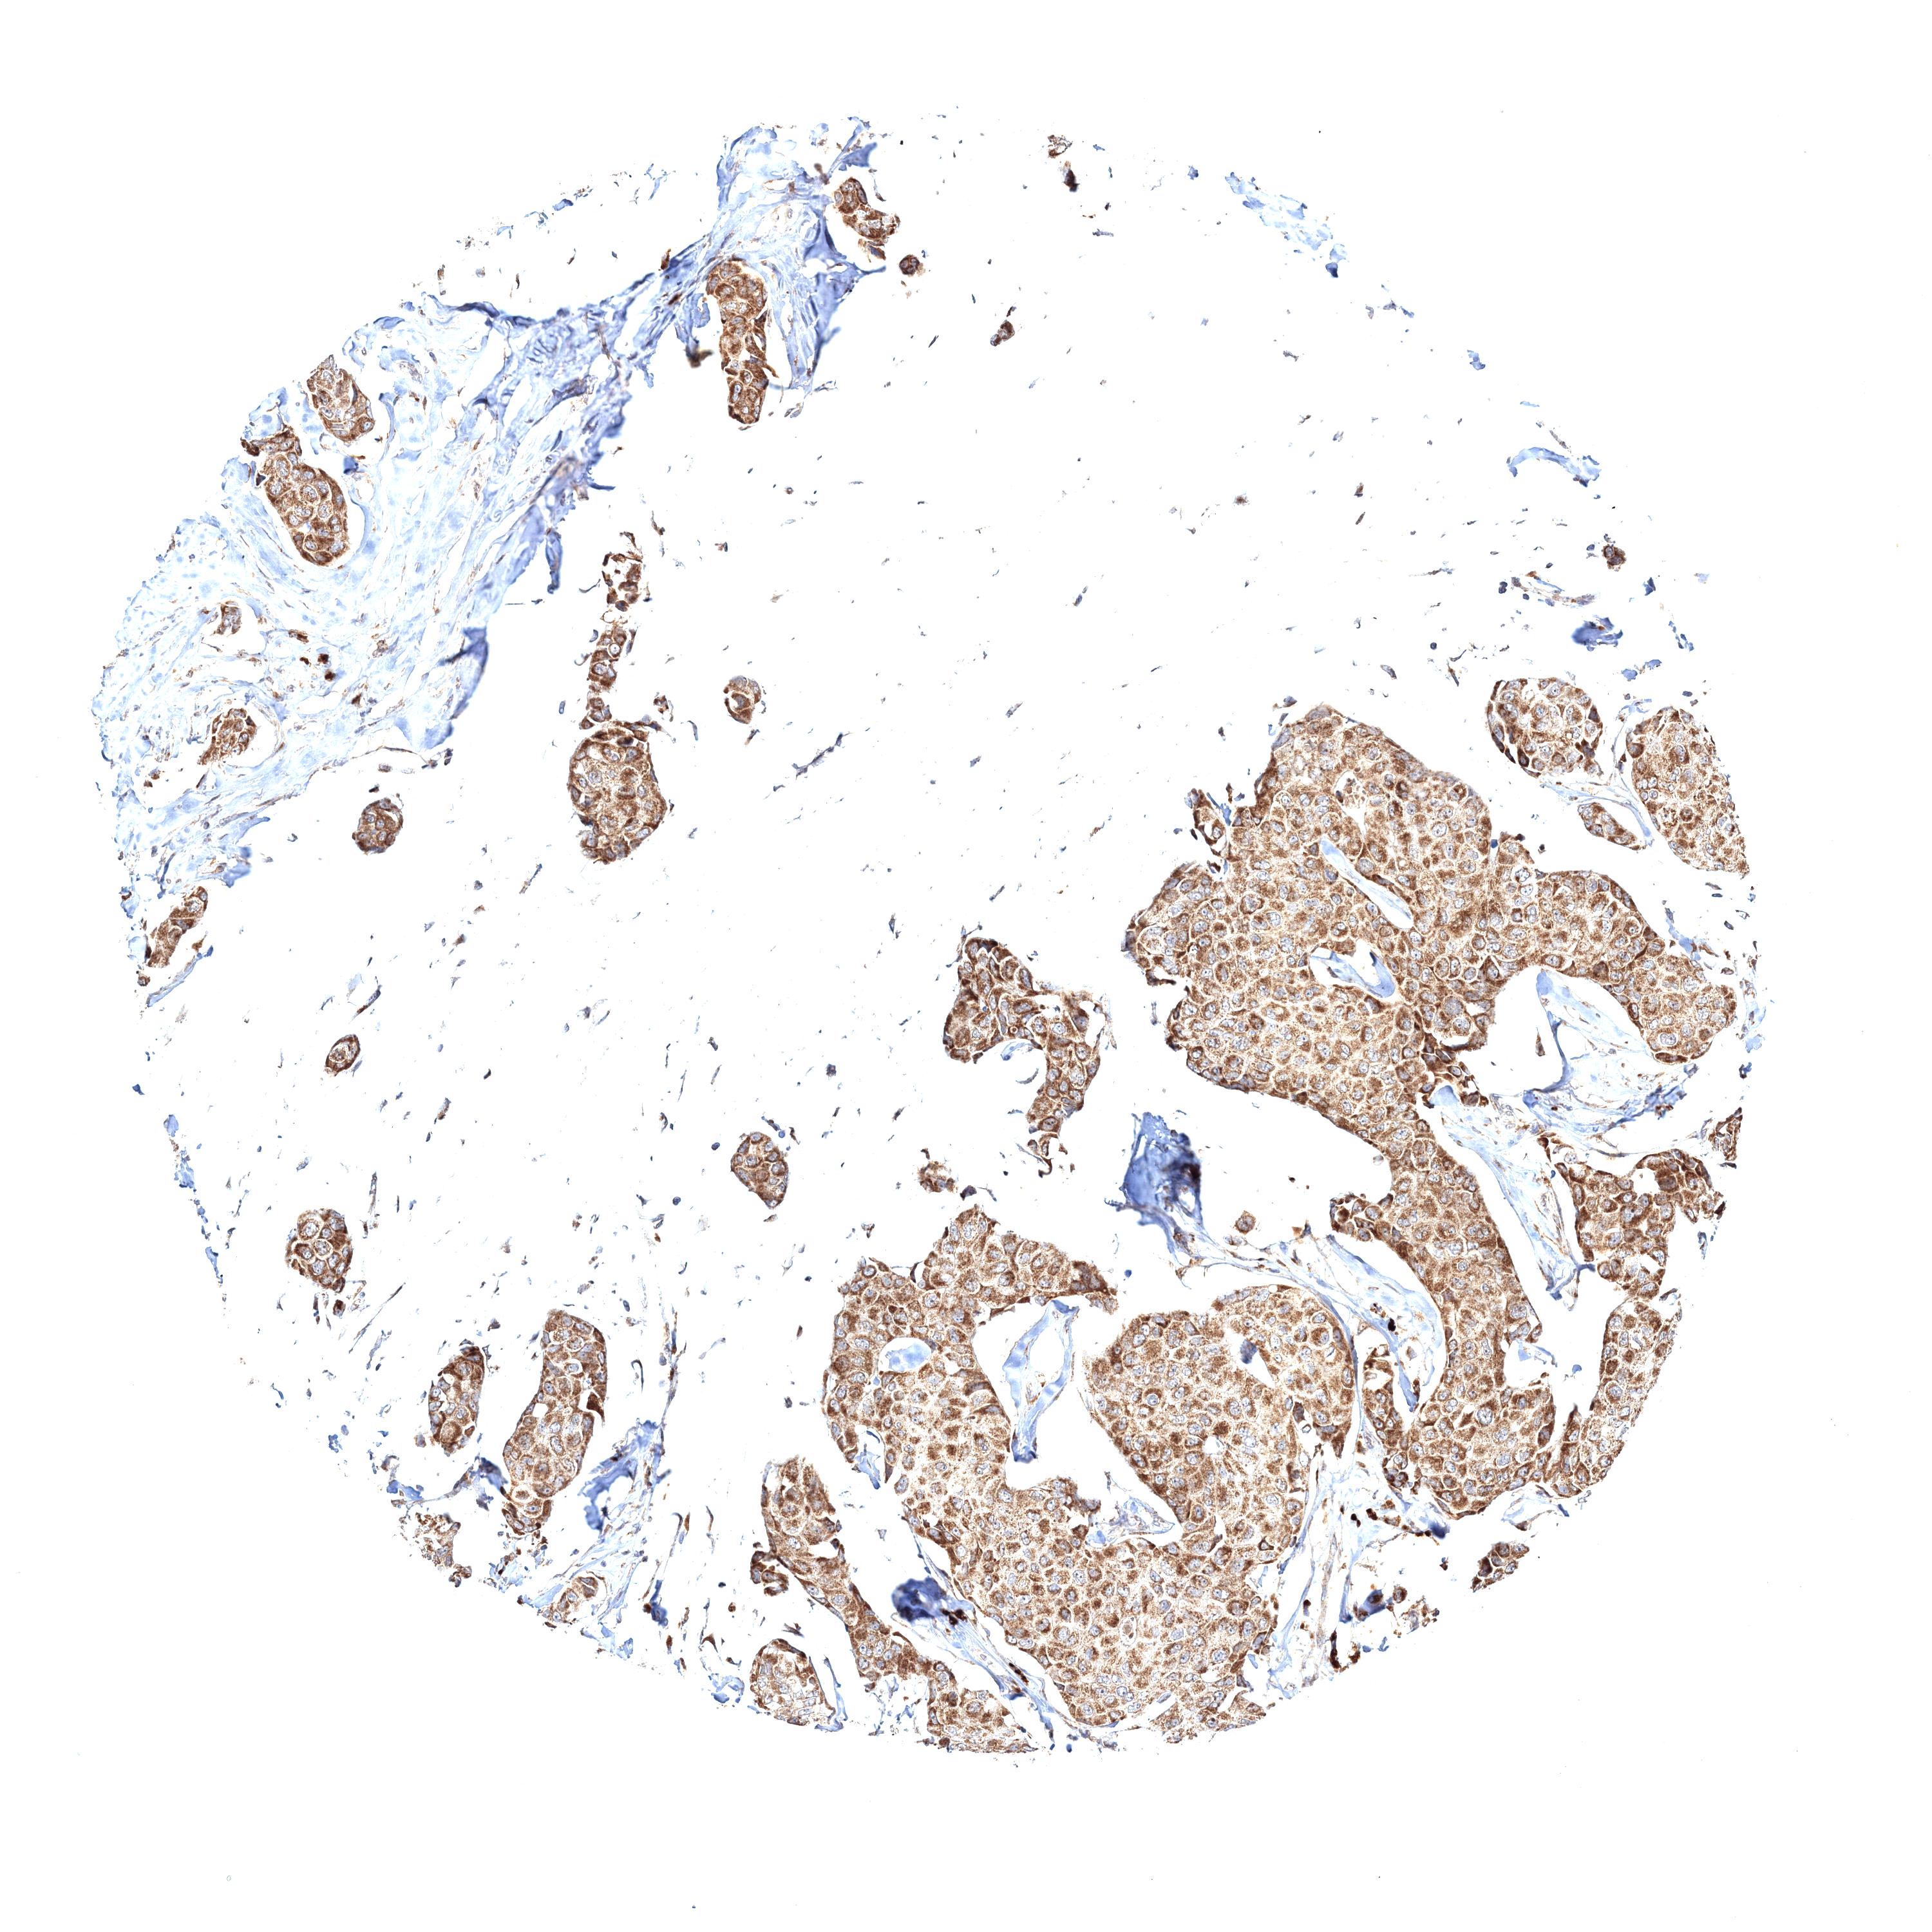

CANCER BREAST CANCER Show tissue menu

BRCA TCGA BRCA VALIDATION PROTEIN EXPRESSION

Breast cancer

Human cancer